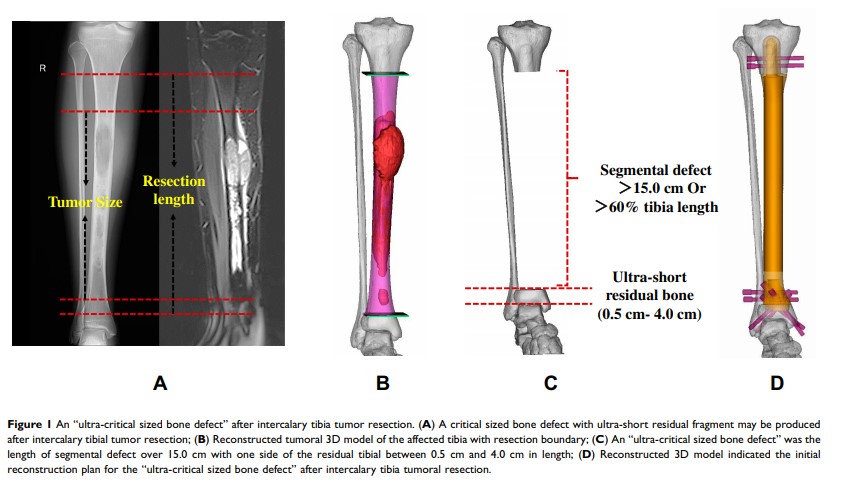

胫骨恶性肿瘤切除术后,通过 3D 打印多孔假体对 “超临界骨缺损” 的修复重建